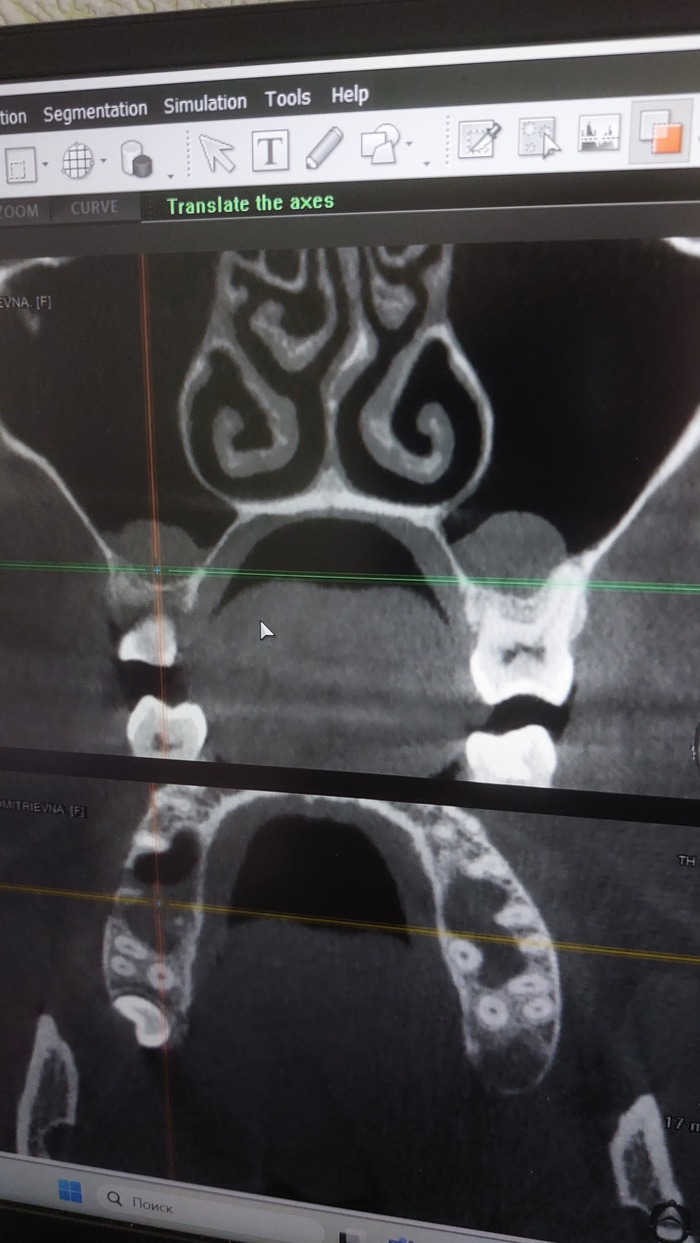

Я иду в клинику, там делают КТ челюсти, говорят что все оставшееся под удаление, процедура восстановления год, года у меня нет, я отказываюсь и ухожу. Слегка расстроена, конечно, но не жили красиво, не будем и начинать, в конце концов альтернатива у меня и так в наличии.

Приезжаю, кабинет у него в бизнес-центре на Обуховской обороны (СПБ), привожу запись кт... Он осматривает, ощупывает мои челюсти, смотреть КТ отказывается ("Это непоказательно, там бывают ложные затемнения, я делаю по необходимости отдельные снимки"), предлагает вариант верх 6 имплантов с немедленной нагрузкой, низ пролечивание пеньков+культевые вкладки+цирконовый мост+ 4 импланта и две конструкции из металоокерамики, там где пеньков нет. про свои ограниченич по срокам я тоже говорила, и сразу озвучила что если так нельзя, ок, я переживу, т.е не настаивала. да я в курсе про большую убыль кости, и это вопрос я задала одним из первых, на что получила ответ "отличная кость, ничего не надо наращивать"

Ну ок, он врач, он больше знает. При этом снимков челюсти за все время было сделано два или три, отдельных мест, где импланты вываливались (это важно, дальше поймете почему)

Врачи сейчас поймут с одного взгляда, не врачи -присмотритесь, где там та сама "отличная кость"? Один имплант держится буквально последним миллиметром.

И да, это та самая сторона которая все время доставляла мне беспокойство, и та где протез сломался.

Если честно, после всего описанного я совершенно не готова проходить этот путь с имплантацией второй раз. У меня снова сверху вставная челюсть, сделали мне ее очень хорошо и аккуратно и если честно мне намного легче с ней жить чем весь предыдущий год. Да, я почти уверена что так потому что протезирование верхней челюсти было сделано плохо. И, справедливости ради должна сказать что что-то таки было сделано хорошо, а именно мост на нижней челюсти. Хотя и там были оставлены недолеченные кисты (см снимок)